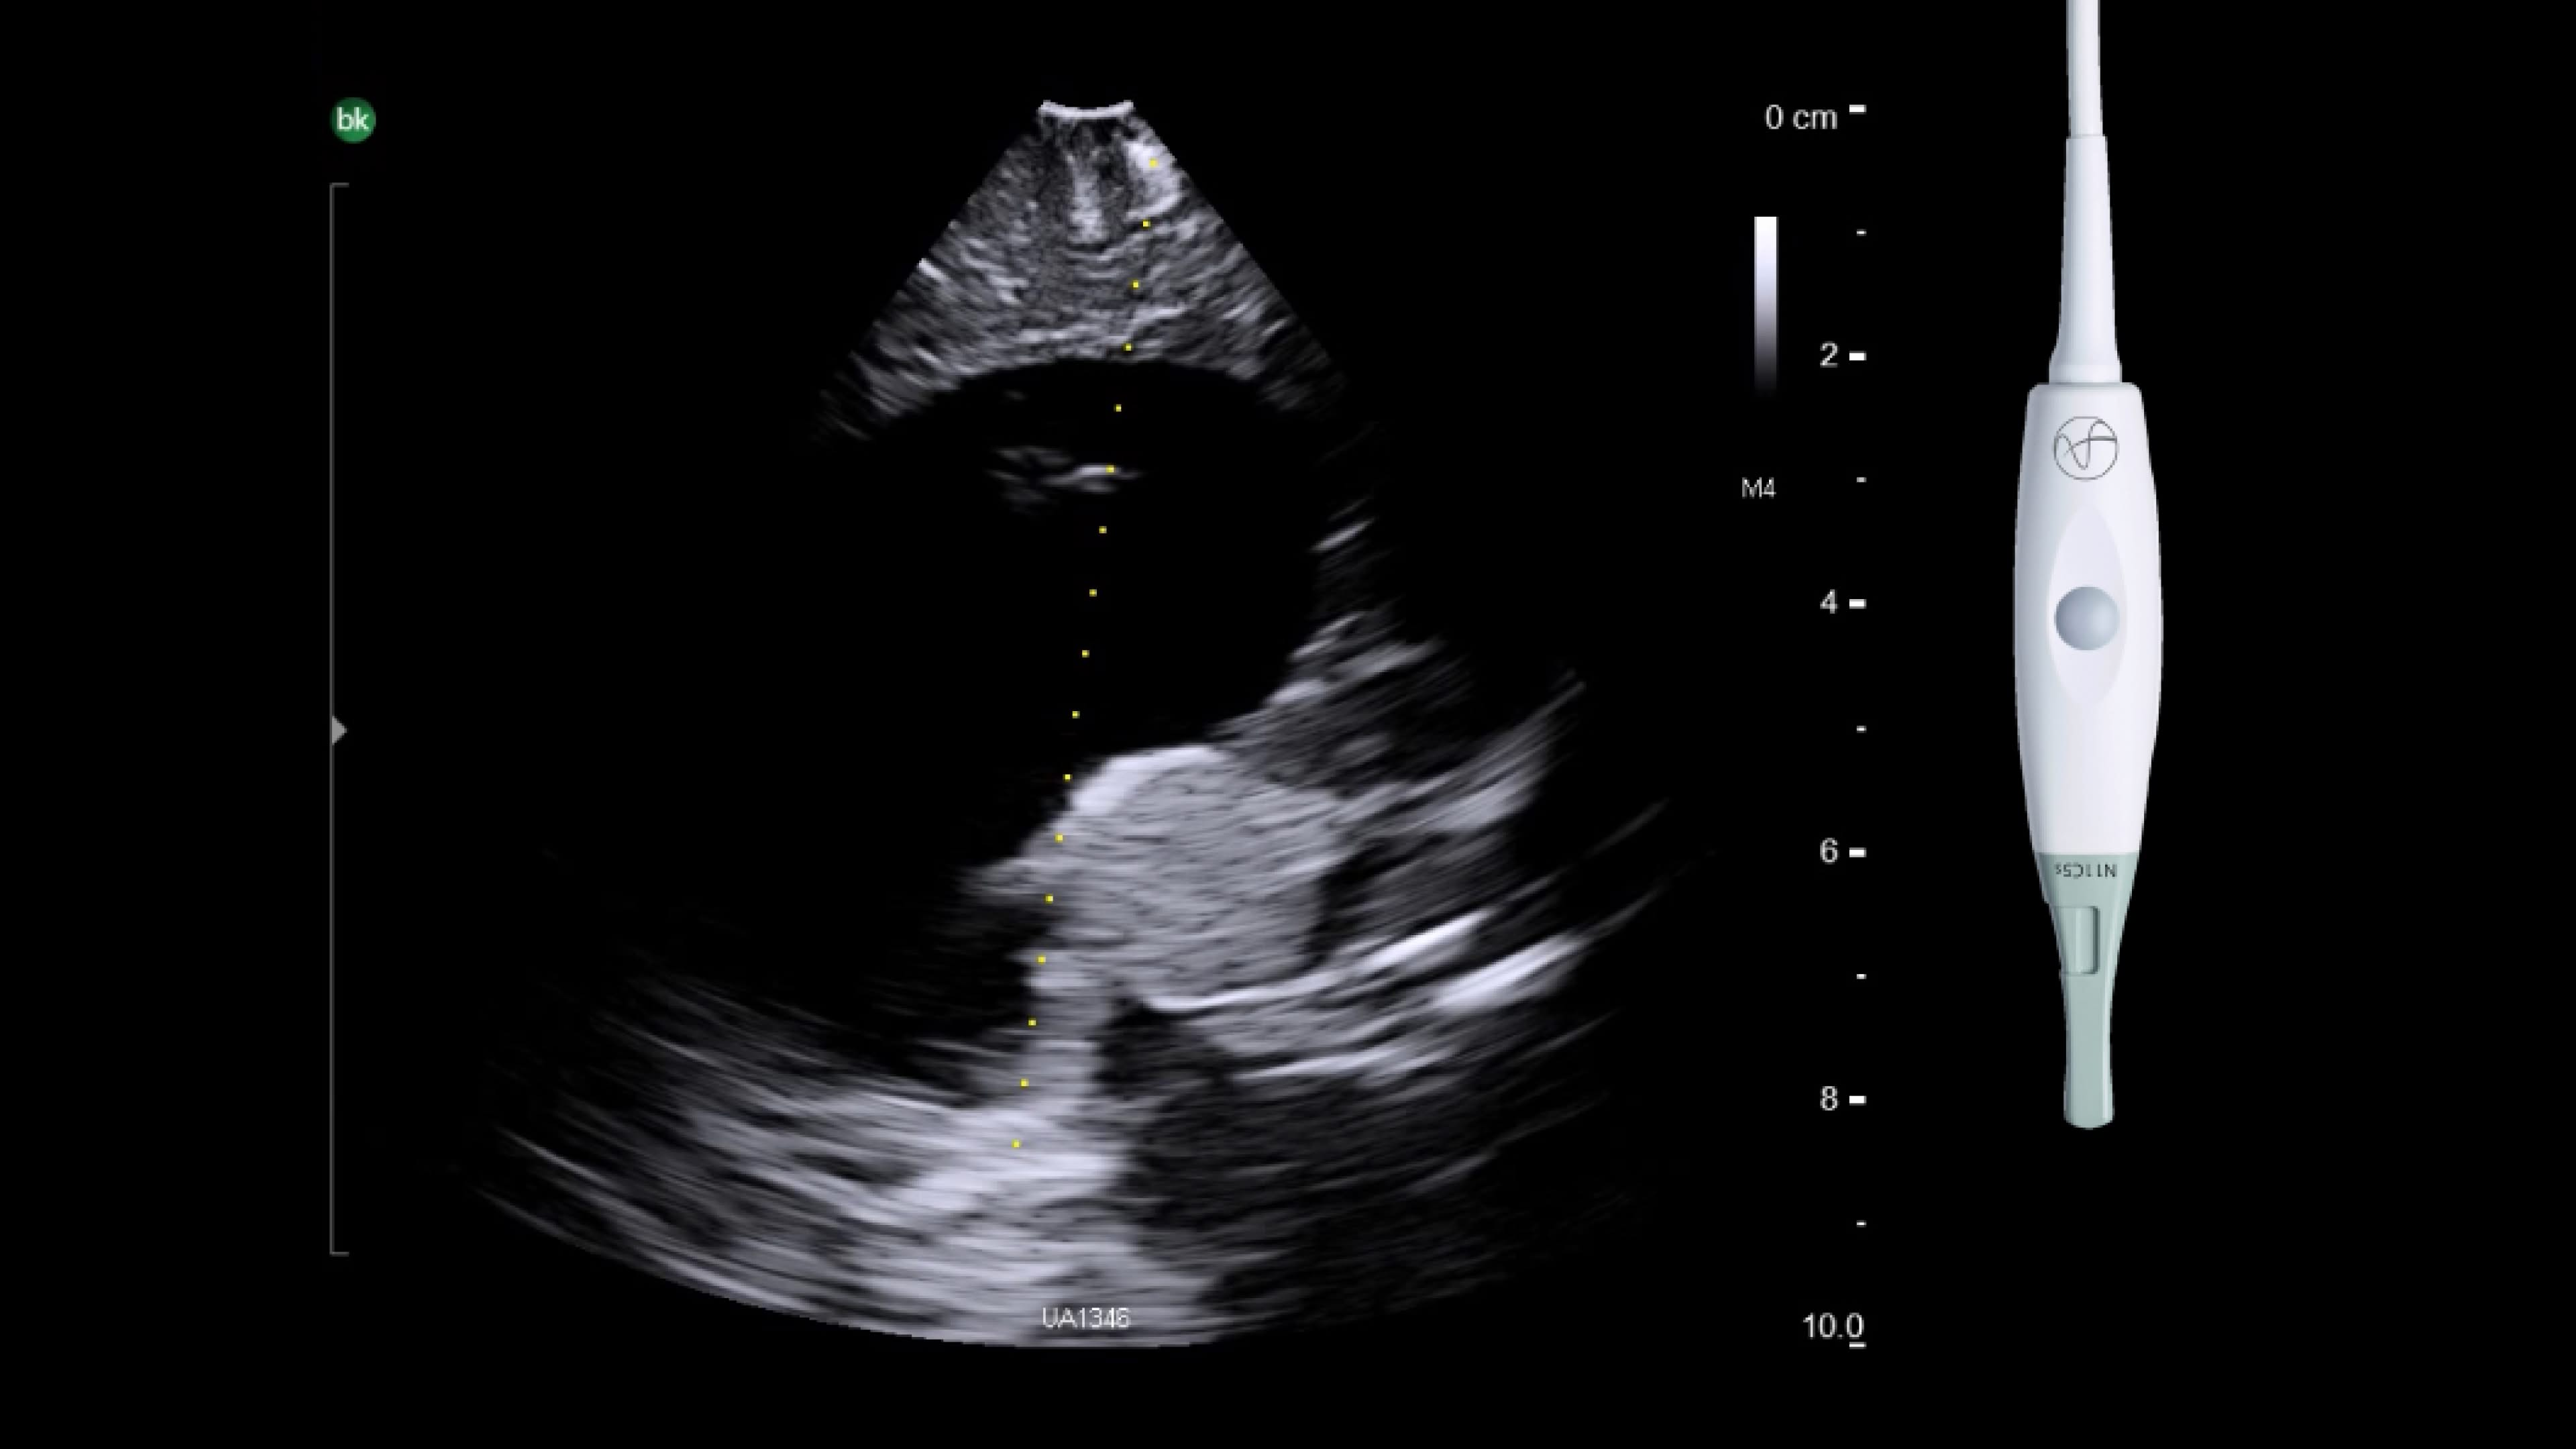

Neuro-oncology

Use intraoperative ultrasound during surgery to assist in the identification of brain shift after pre-operative scans and determine extent of resection and assess for residual tumor.